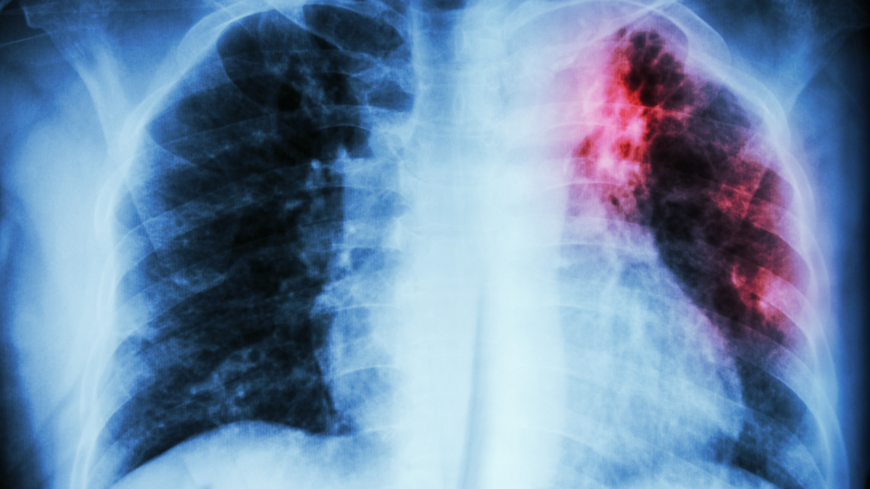

Tuberkulos är en infektionssjukdom som främst påverkar lungorna. Foto: Shutterstock

Tuberkulos, TBC, är en infektionssjukdom som främst påverkar lungorna men även vissa andra organ i kroppen.